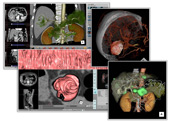

■医用画像処理ワークステーション「ZIOSTATION」

高度な画像処理を実現する「ZIOSTATION」は画像処理機能がさらに充実し,より高精度な画像を作成できるようになりました。さらに改善された高度な自動骨除去で,熟練者の技術を必要とした画像処理を自動化機能でサポートします。豊富なオプションと高速画像処理で画像診断を強力にサポートします。

医用画像処理ワークステーション「ZIOSTATION」

【画像クリックで拡大表示します 】